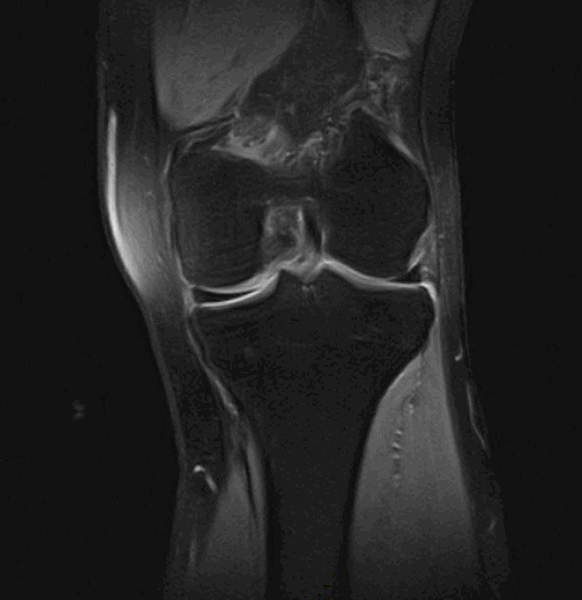

Фронтальный срез МРТ коленного сустава

На МРТ хорошо прослеживаются все стадии этого процесса. На томограмме определяется выпот синовиальной жидкости и подхрящевая костная киста при остеоартрозе коленного сустава.

МРТ точно визуализирует все степени изменения хряща от отека до истончения, разволокнения и растрескивания. Оценивается состояние подхрящевой костной ткани, изменения в менисках, воспаление синовиальной оболочки и так далее.

Возможен расчет общего объема пораженного хряща и измененных участков кости, оценивается состояние крестообразных связок.